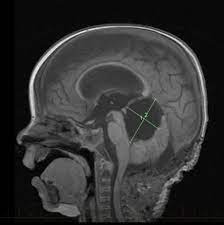

Что такое атипичная тератоид-рабдоидная опухоль?

АТРО относится к группе редких, но агрессивных опухолевых патологий, характеризуемых быстрым ростом и способностью возникать сразу в нескольких местах организма. Локализуется в мышечной ткани, в забрюшинном пространстве, органах средостения, в поясничном, шейном или грудном отделе спинного мозга. В состав опухоли могут входить как рабдоидные, так и нейроэпителиальные, мезенхимальные клетки, Формирование образования чаще всего провоцирует изменение в работе гена-супрессора, который из-за дефекта перестает контролировать рост опухоли. Связывают это с герминативной мутацией – врожденной патологией, передающейся на генетическом уровне.

При подозрении на злокачественное новообразование ЦНС проводится комплексное обследование, чтобы выявить вид и форму опухоли, ее расположение и степень распространения, сопутствующие осложнения. Маленькому пациенту на основании характерных симптомов проводится осмотр, генетическое обследование, неврологическое тестирование с проверкой функционирования спинного мозга. Также выполняются инструментальные исследования для визуализации опухоли, выполняется биопсия, чтобы в лабораторных условиях изучить взятый материал на определение конкретного вида. АТРО не имеет стандартных стадий, классифицируясь как первичная или рецидивирующая болезнь. Исходя из этого в дополнении к полученной путем диагностики информации, подбирается лечебный план.